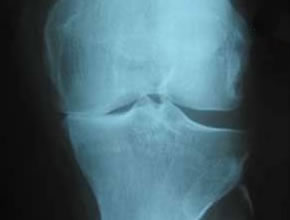

Orthopädie und Unfallchirurgie sind die medizinischen Fachbereiche, die sich mit dem gesamten Bewegungsapparat (Knochen, Gelenke, Muskulatur etc.) beschäftigen. Dabei werden Verschleißerkrankungen (z. B. Arthrose), Fehlstellungen (z. B. Skoliose) und Verletzungen (z. B. Knochenbrüche) untersucht und behandelt.